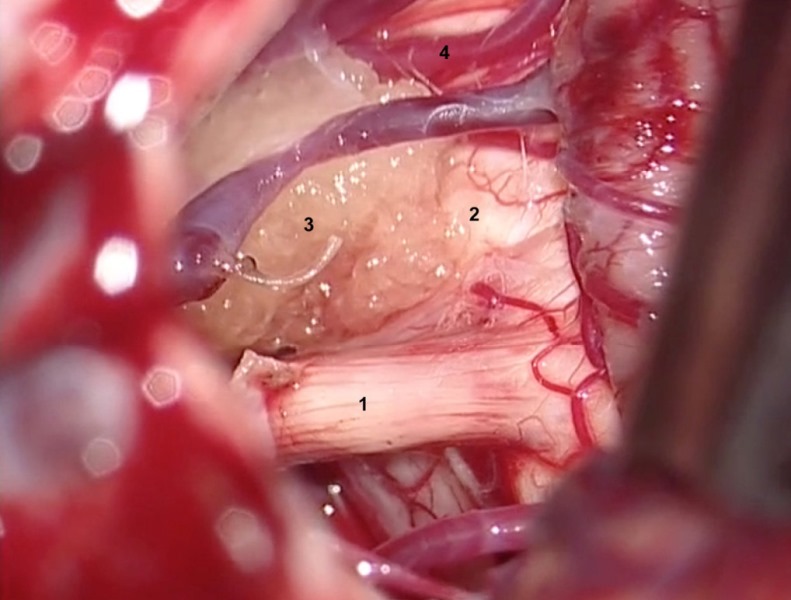

3. Arteries and/or veins compressing the V pair must be dissected from the nerve. The nerve must be inspected and freed from the arterial vessels from its origin in the brainstem to its entry into the cavum of Meckel 18. The veins can be coagulated and then divided (to avoid recanalisation) ( Figures 6 B and C).

1. Trigeminal nerve.

2. Pons.

3. Superior cerebellar artery compressing the nerve medially.

4. Superior petrous vein.

3. Superior cerebellar artery.

4. Middle cerebellar peduncle.

4. The artery most frequently compressing the trigeminal nerve is the superior cerebellar artery.